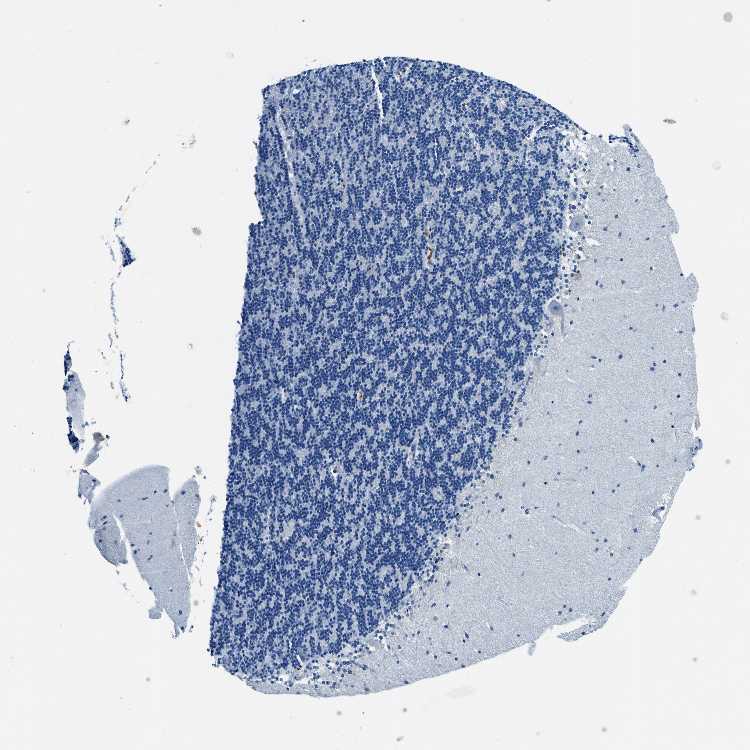

CEREBELLUM - Antibody stainingi

Antibody staining in the annotated cell types in the current human tissue is reported as not detected, low, medium, or high, based on conventional immunohistochemistry profiling in selected tissues. This score is based on the combination of the staining intensity and fraction of stained cells.

Each image is clickable and will lead to virtual microscopy that enables deeper exploration of all samples and also displays staining intensity scores, fraction scores and subcellular localization as well as patient and tissue information for each sample.

Antibody HPA013448

Purkinje cells Not detected

Cells in granular layer Not detected

Cells in molecular layer Not detected